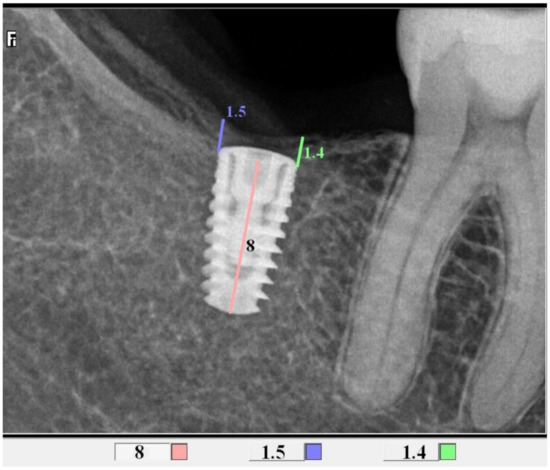

2.4. Radiological Assessment of the Bone Level in the Proximity of the Implant

| Implant lenth | 8 mm | 8 (18.60%) | 13 (27.08%) | 10 (32.26%) | 31 (25.41%) | 0.71 |

| 10 mm | 30 (69.77%) | 31 (64.58%) | 19 (61.29%) | 80 (65.57%) | F | |